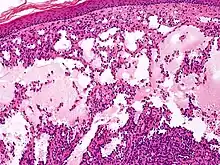

Microscopically, the vesicles in lymphangioma circumscriptum are greatly dilated lymph channels that cause the papillary dermis to expand. They may be associated with acanthosis and hyperkeratosis. There are many channels in the upper dermis which often extend to the subcutis (the deeper layer of the dermis, containing mostly fat and connective tissue). The deeper vessels have large calibers with thick walls which contain smooth muscle. The lumen is filled with lymphatic fluid, but often contains red blood cells, lymphocytes, macrophages, and neutrophils. The channels are lined with flat endothelial cells. The interstitium has many lymphoid cells and shows evidence of fibroplasia (the formation of fibrous tissue). Nodules (A small mass of tissue or aggregation of cells) in cavernous lymphangioma are large, irregular channels in the reticular dermis and subcutaneous tissue that are lined by a single layer of endothelial cells. Also an incomplete layer of smooth muscle also lines the walls of these channels. The stroma consists of loose connective tissue with a lot of inflammatory cells. These tumors usually penetrate muscle. Cystic hygroma is indistinguishable from cavernous lymphangiomas on histology.[4]